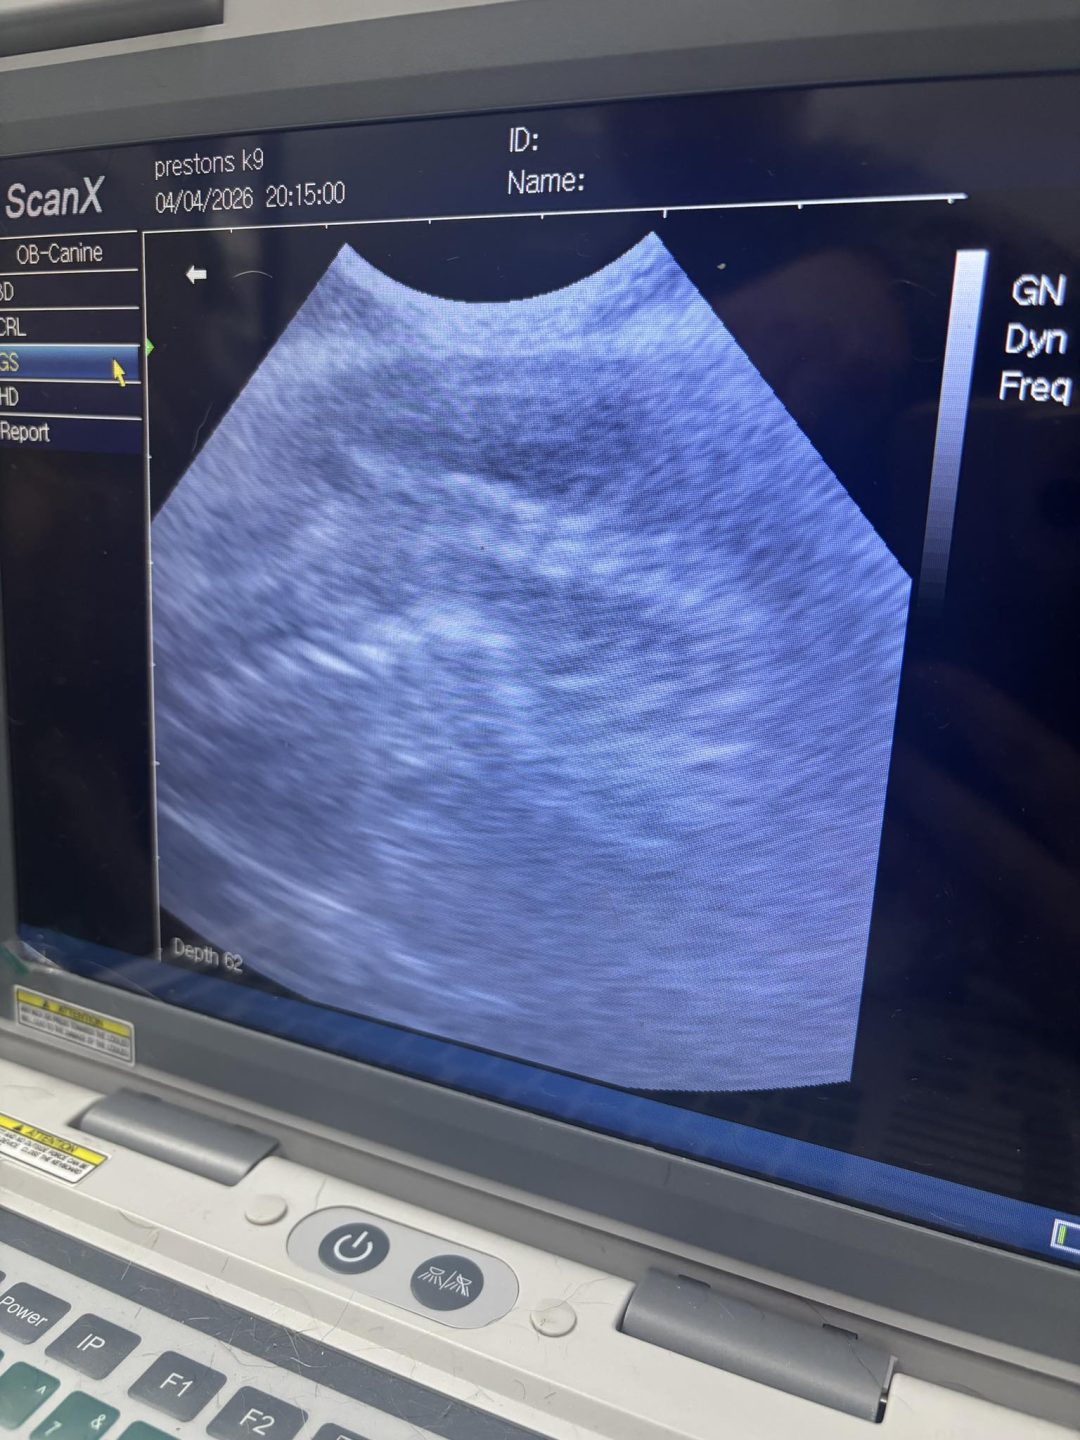

Ultrasound check-up scan carried out today here at Preston’s K9 fertility services on a mini dachshund with about a week left of pregnancy

Puppies are all looking great. Located heartbeats, spines and ribs

An estimated pup count of five